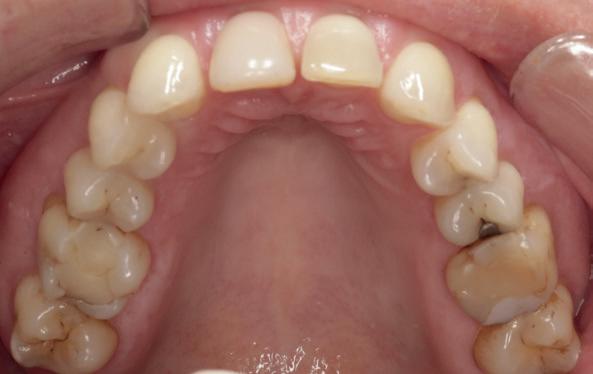

Na parodontale stabiliteit werd de derde behan-

delstap geïnitieerd. De beet werd geregistreerd in centrale relatie en er werden zowel intra- als extraorale (studio)opnamen vervaardigd. Klinisch werd een end-to-end beet in combinatie met een kruisbeet vastgesteld. Voor het realiseren van een duurzame restauratieve rehabilitatie werd uitgegaan van een functioneel gebalanceerde occlusie, gebaseerd op het mutual protection concept: in centrale occlusie zorgen de molaren en premolaren voor verticale stabiliteit en dragen zij de kauwkrachten. Tijdens dynamische bewegingen, zoals protrusie en laterotrusie, nemen de voortanden de geleiding over en worden de posterieure elementen ontlast. Dit principe, waarbij posterior de beet draagt en an-

terior de bewegingen stuurt, voorkomt overbelasting van het parodontium en draagt bij aan de duurzaamheid van de restauraties. In deze casus was het herstellen van dit functionele evenwicht essentieel om zowel esthetiek als kauwfunctie voorspelbaar te herstellen. In samenwerking met het tandtechnisch laboratorium werd bestudeerd of de bestaande malocclusie prothetisch kon worden gecorrigeerd, zonder orthodontie of orthognatische chirurgie. Dit bleek goed mogelijk te zijn.

9). In de bovenkaak werd bilateraal een sinuslift uitgevoerd. Aansluitend werden in beide kaakhelften implantaten geplaatst (afbeelding 10).

Ter beoordeling van het gewenste eindresultaat, werd een additieve wax-up vervaardigd. Deze werd met behulp van een siliconenmal en chemisch-hardende kunsthars omgezet in een intra-orale mockup (afbeelding 11). Ondanks de grove aard van deze voorlopige vormgeving bood deze voldoende diagnostische waarde om esthetiek en functie te beoordelen. Tevens faciliteerde de mock-up gedeelde besluitvorming tussen behandelaar en patiënt. Op basis van intra- en extraorale opnamen en een mondscan van de mock-up werd het ontwerp in overleg met het tandtechnisch laboratorium verder geoptimaliseerd (afbeelding 12).

13. Techniekmodel

plaatsing van de restauraties werden zowel de tandboog als de tandstand in de bovenkaak gecorrigeerd (afbeelding 13-15).

Aansluitend werd de onderkaak volgens hetzelfde principe gerehabiliteerd, resulterend in een stabiele, functionele en esthetisch gebalanceerde occlusie (afbeelding 16-17).